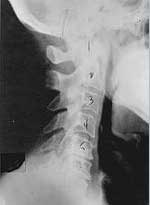

Phase two subluxation degeneration is normally seen in subluxations that have been present between 20 and 40 years. This phase has some of the same characteristics of the previous phase including a loss of normal curvature and position as well as an alteration in segmental motion. In addition, spines with Phase Two Subluxation Degeneration many times show a reduction in the patient's range of motion in that area. X-rays of a phase two begin to show calcium changes or buildup at certain levels of the spine. These changes are sometimes called by many names including spurs and arthritis. Disc spaces between the affected vertebrae are noticeably narrower and may appear to be flattening out. Although most people with Phase Two Subluxation Degeneration may not exhibit any symptoms, some may start to feel stiff or achy. Chiropractic reconstructive care for patients in phase two ranges from 1.5 years to 2.5 years. Again, if Phase Two Subluxation Degeneration is left uncorrected it slowly advances to the next phase.